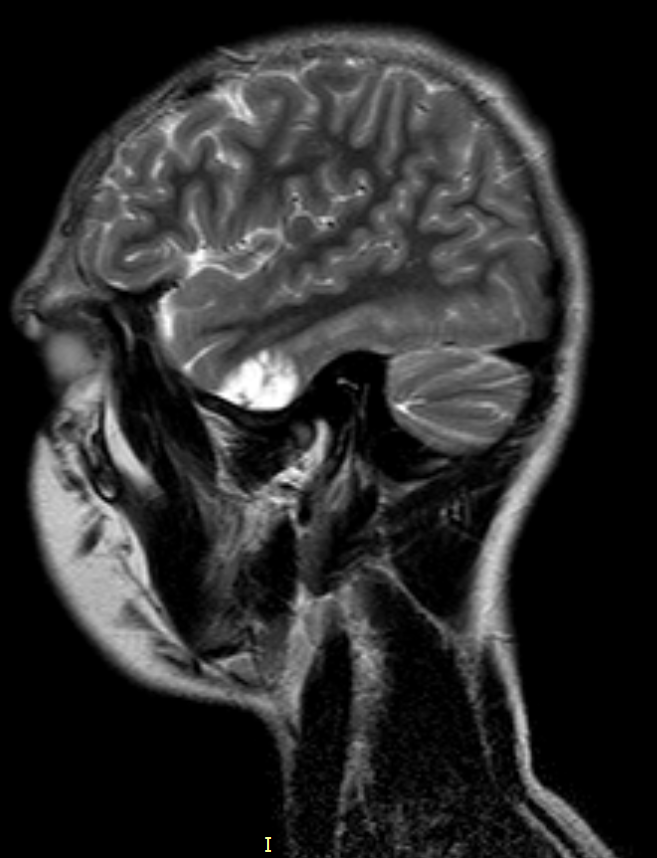

Внутричерепная гипотензия: КТ-исследования и их интерпретация

Раздел: Образы вокруг